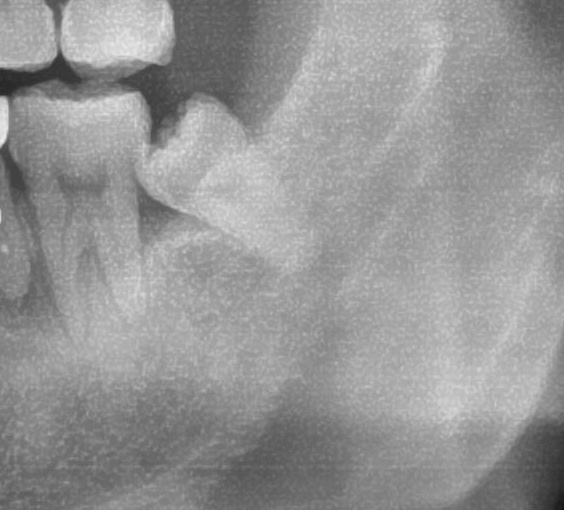

次にパノラマ写真を撮影してみると、左下の親知らずは歯茎の中で手前の歯を押すように斜めに生えているのが確認できました。

親知らずが生えている位置が、神経に近い、あるいは神経に当たっている場合は、大きな病院に紹介する場合もあります。

親知らずの根っこは下歯槽神経からは十分距離があるようです。